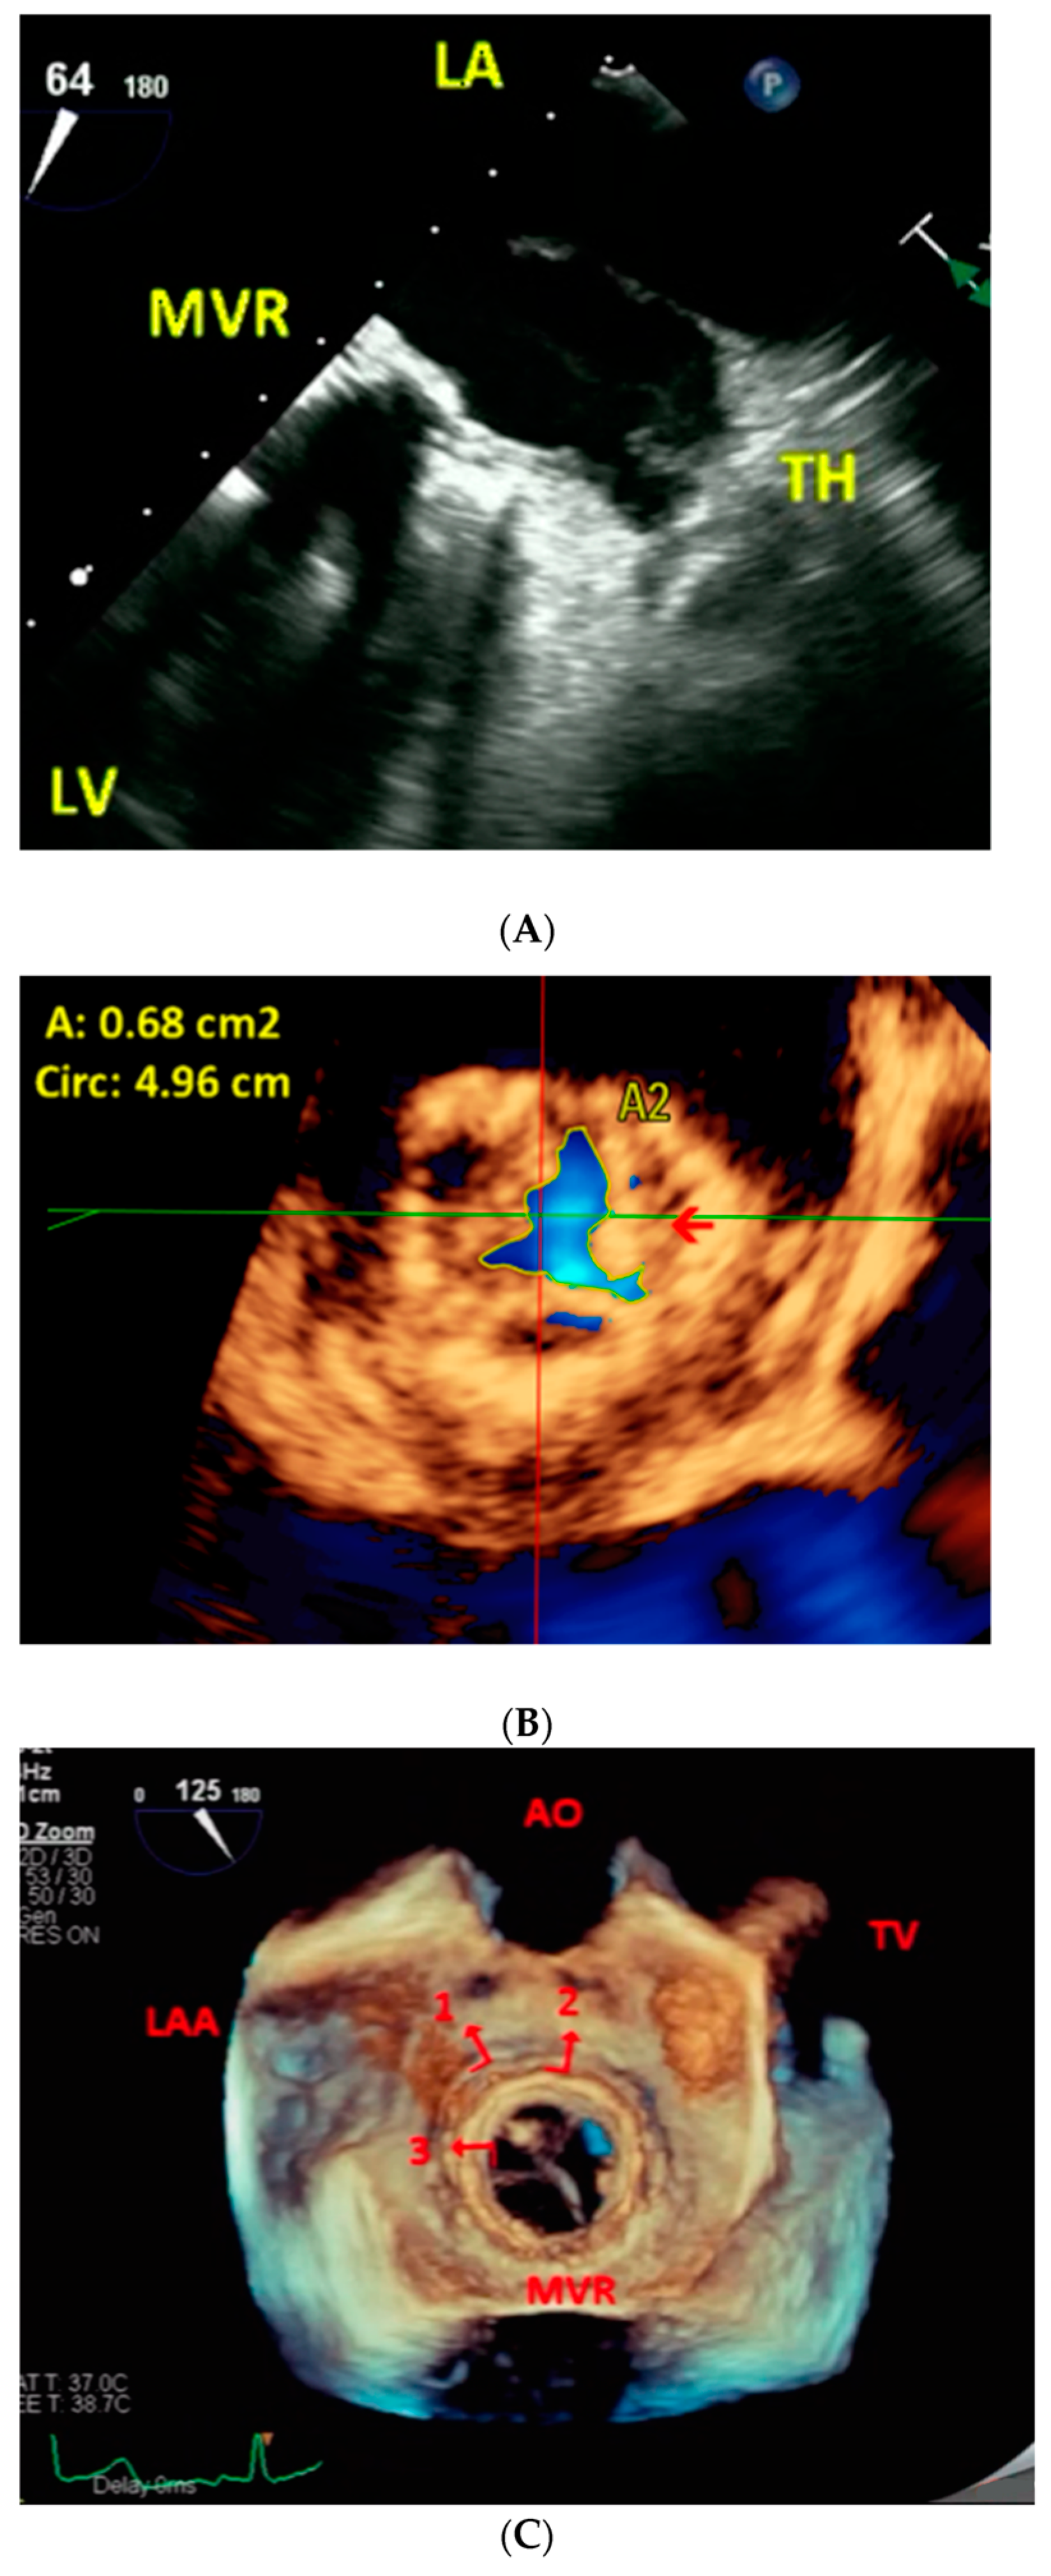

Figure 1. (AK), Video S1. 78-year-old female with severe bioprosthetic mitral valve stenosis (Case 10). Pre-procedure. Two-dimensional transthoracic echocardiography with color Doppler guided continuous wave Doppler in (A) shows a mean pressure gradient (PG) of 14 mmHg across mitral valve replacement (MVR) consistent with severe stenosis. Two-dimensional transesophageal echocardiography (B,C) using the same technique as in (A) shows a mean pressure gradient of 13.1 mmHg across MVR also consistent with severe stenosis in (B). Turbulent flow across MVR as well as a thrombus (TH) in the left atrial appendage (LAA) and adjacent left atrium (LA) body are demonstrated in (C). Live/real-time three-dimensional transesophageal echocardiography (DG, Video S1). The arrow in (D) points to the MVR orifice which measures 0.72 cm2 in multiplanar reconstruction (MPR) mode consistent with severe stenosis. Viewing the LA body en face by cropping the full volume dataset from below shows the TH (arrows) extending to near the MVR in (E). Video S1 shows both fixed (left arrow) and mobile (right arrow) components of the TH. The right upper panel in F shows the TH involving LAA almost completely and extending to the adjacent LA body (arrow). The arrow in the right lower panel shows the TH adjacent to the aorta (AO). The arrow in the left lower panel shows the TH adjacent to PA. The combined volume of the TH in LAA and adjoining LA body measured 19.4 mL as shown in (G). During Procedure. Two-dimensional transesophageal echocardiography (H). The lower arrow in H shows the catheter deployment device passing through MVR and lodged in the left upper pulmonary vein (UPV). The upper arrow points to the TH which was bypassed during the procedure. Live/real-time three-dimensional transesophageal echocardiography (I). The vertical arrow in (I) points to the catheter deployment device bypassing and avoiding the TH (horizontal arrow). Post-procedure. Two-dimensional transesophageal echocardiography (J). Color Doppler directed continuous wave Doppler examination in 4 chamber view in J shows a marked decrease in the mean pressure gradient across the new MVR to 1.8 mmHg indicative of relief of stenosis. Live/real-time three-dimensional transesophageal echocardiography (K). In (K), #1 and #2 represent the old and new prosthetic valve rings, respectively, in full volume short-axis view. LV = left ventricle; PA = pulmonary artery; RA = right atrium; RV = right ventricle; RVO = right ventricular outflow. PV = pulmonary valve.